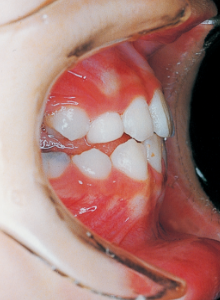

17 8-15-’94 After Retention 14 years and 7 months after start of treatment

Reflecting on the course of treatment, one cannot help but marvel at the strength of the inherent biological program. At the same time, it makes one ponder how much artificial influence the body can allow and adapt to. While it would be difficult to say the long-term work in the first phase was suddenly meaningless, we must consider how much value it held for the overall treatment. The tongue is always positioned low due to its anatomical relationship within the facial structure. While it is understood that this low tongue position affects the dental arch, current treatment methods offer no solution. In such cases, we are acutely aware of the limited scope of what we can do.